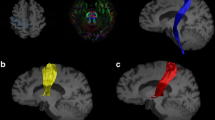

For ROI-based estimation of diffusion parameters, ROIs were outlined manually on parameter maps by one trained investigator (YS). All ROIs were outlined twice with an interval of 3 months (average intra-rater variability >0.9 for all ROIs). FA- and directionally color-encoded FA maps were used to outline all ROIs, except for the RN and deep cerebellar nuclei (DCN), where the non-diffusion-weighted map was used (Fig. 1). The ROI size was adjusted in each subject to maximize coverage of each structure, while minimizing partial volume effects from neighboring areas. Contamination from cerebrospinal fluid (CSF), which has isotropic diffusion with a high MD, was avoided by excluding voxels adjacent to the third and lateral ventricles.

Fig. 1 Region of interests in subcortical structures and the superior cerebellar peduncle and tractography of the dentatorubrothalamic tract. Region of interests (ROIs) are placed in a the putamen, caudate head, thalamus; b the ventral anterior and ventral lateral nuclei of the thalamus (VL), green colored voxels and the lateral posterior nucleus and ventral posterior nuclear complex of the thalamus, violet colored voxels; c the red nucleus; d the pons and midbrain; e superior cerebellar peduncle (SCP); f deep cerebellar nuclei (DCN); g the left and right dentatorubrothalamic tract defined by ROIs were placed in DCN, SCP, and contralateral VL

The head of the caudate nucleus was delineated in a single slice at the level where it was most conspicuous. The thalamus and putamen were delineated in 5–8 consecutive slices at the level of the internal capsule, the thalamus adjacent to the interthalamic adhesion, and the putamen to the extreme capsule. The VA and VL nuclei of the thalamus (VAVL) were identified on FA color maps as green voxels (Fig. 1) [31, 32], in the anterior part of the lateral thalamus close to the genu of the internal capsule, while excluding the three most medial voxels that were regarded to comprise the medial dorsal nuclei. The lateral posterior nucleus (LP) and ventral posterior (VP) nuclear complex of the thalamus (LPVP) were identified on FA color maps as violet voxels (Fig. 1) [31, 32] adjacent to the posterior limb of the internal capsule and anterior to the pulvinar in red. The RN was identified as a circular area of signal hypointensity in the midbrain on non-diffusion-weighted maps and delineated in at least two consecutive axial slices. The SCP was delineated on two consecutive sagittal slices. The midbrain and the pons were delineated on five consecutive sagittal slices, with ROIs including the whole structure. The manual approach proposed by Oba et al. [33] was used to identify the boundaries of the pons and the midbrain. For each structure, the average FA and MD value from the right and left hemisphere was calculated.

TBSS (v 1.03), part of the FRMIB Software Library (FSL), was employed as a complementary analysis tool for diffusion parameters in the thalamus. Comparisons were performed in PSP vs controls in the derivation cohort and in PSP vs controls, PD and MSA-P in the validation cohort (Fig. 2) [34]. FA and MD maps were registered onto the 1 mm3 FMRIB58 FA template in MNI152 standard space, using the linear and nonlinear registration tools FLIRT and FNIRT [35, 36]. Before registration, the diffusion maps were masked with the FSL Brain Extraction Tool (BET) [37]. The normalized maps were skeletonized by projection onto the FMRIB58 template skeleton. Finally, the skeletonized maps were masked to include only voxels from the thalamus. The masking was done using the left and right thalamus regions in the MNI152 space Harvard-Oxford subcortical atlas, together with the requirement that the MD of the normalized maps must be less than unity in the control subjects of the derivation cohort [38].

Fig. 2 Areas in thalamus with significantly decreased fractional anisotropy and increased mean diffusivity in patients with progressive supranuclear palsy when compared to healthy controls. Results of the tract-based spatial statistics (TBSS) analysis in the thalamus, showing regions of significant decreased fractional anisotropy (red voxels) and increased mean diffusivity (blue voxels) in patients with progressive supranuclear palsy when compared to healthy controls. a and b correspond to the derivation cohort, while c and d correspond to the validation cohort. Green voxels are voxels on the TBSS-skeleton where no significance was found

For probabilistic tractography of the DRTT, its inferior and superior part were constructed each using a seed ROI placed in the DCN and VAVL of the contralateral thalamus, respectively, and an include ROI in the SCP (Fig. 1). The left and right DRTT were then constructed by combining the inferior and superior DRTT into one tract, selecting fibers passing through include ROIs in these three locations, DCN, SCP, and VAVL. All tracts were visually inspected. The tractography procedure did not generate tracts in two controls from the derivation cohort (unilaterally) as well as in four PSP patients (one patient bilaterally and three unilateral) and one control (unilateral) in the validation cohort.

In the derivation cohort, PSP patients showed significantly higher MD than controls in 75 % of the skeletonized voxels in the thalamus (Fig. 2). In the validation cohort, patients with PSP were found to have a higher MD in the thalamus than controls (75 % significant voxels). In the derivation cohort, a higher MD was also found in the PSP group compared to both PD (67 % significant voxels) and MSA-P (53 % significant voxels). Furthermore, a reduced FA was observed in PSP vs controls in both cohorts and in PSP vs IPD in the derivation cohort (30–50 % significant voxels).